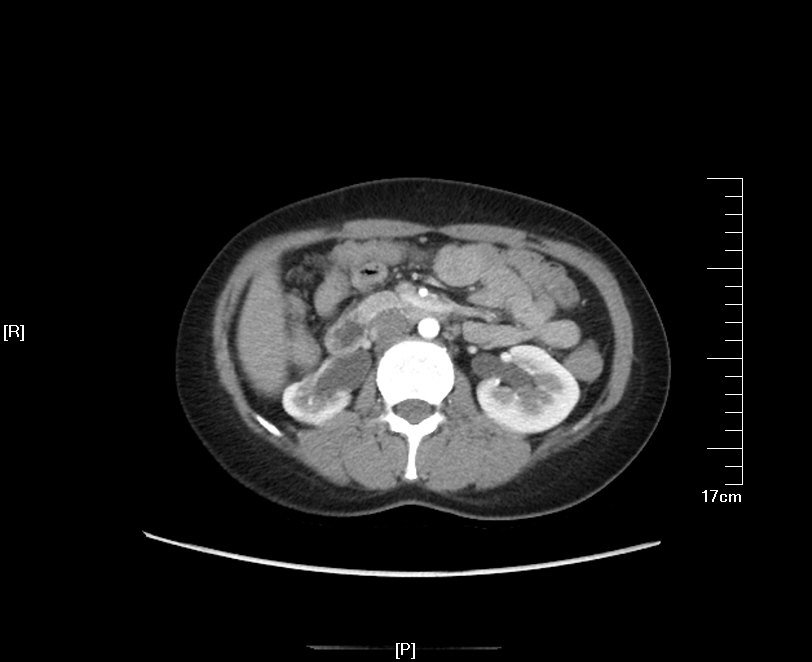

2016年02月手术患者,男性,47岁,河北人,农民,主诉双侧腰部酸胀一年余,伴尿少三天;五年前曾因输尿管结石在当地予以震波碎石3次,后疼痛缓解后未重视,五年来未予以复查,三天前出现尿少,腰部酸胀加重与当地医院就诊后发现病情危重遂来我院求诊,CT:双侧肾脏重度积水,皮质菲薄,双侧输尿管上段扩张明显,双侧输尿管中段结石,左侧结石约1.7cm,右侧约2.8cm左右,GFR:左侧11.7ml/min,右侧16.1ml/min。肾功能:Cr 516umol/L;术前诊断:双侧输尿管结石 双肾重度积水 肾功能失代偿;行双侧经皮肾穿刺造瘘术,保护肾功能,十天后Cr下降至236umol/L,方行双侧输尿管镜检,但由于输尿管梗阻时间太长,输尿管迂曲扩张明显,中段输尿管与周围脏器严重黏连,输尿管镜无法顺利上行,遂行双侧输尿管切开取石术+双侧输尿管裁剪成型术。

CT检查提示:双侧肾脏重度积水双侧输尿管中段结石 双侧输尿管上段积水扩张

入院后行双侧经皮肾穿刺造瘘术,保护肾功能,十天后Cr下降至236umol/L,顺行造影检查发现双侧输尿管迂曲扩张明显,双侧输尿管结石完全梗阻,造影剂无法进入膀胱。